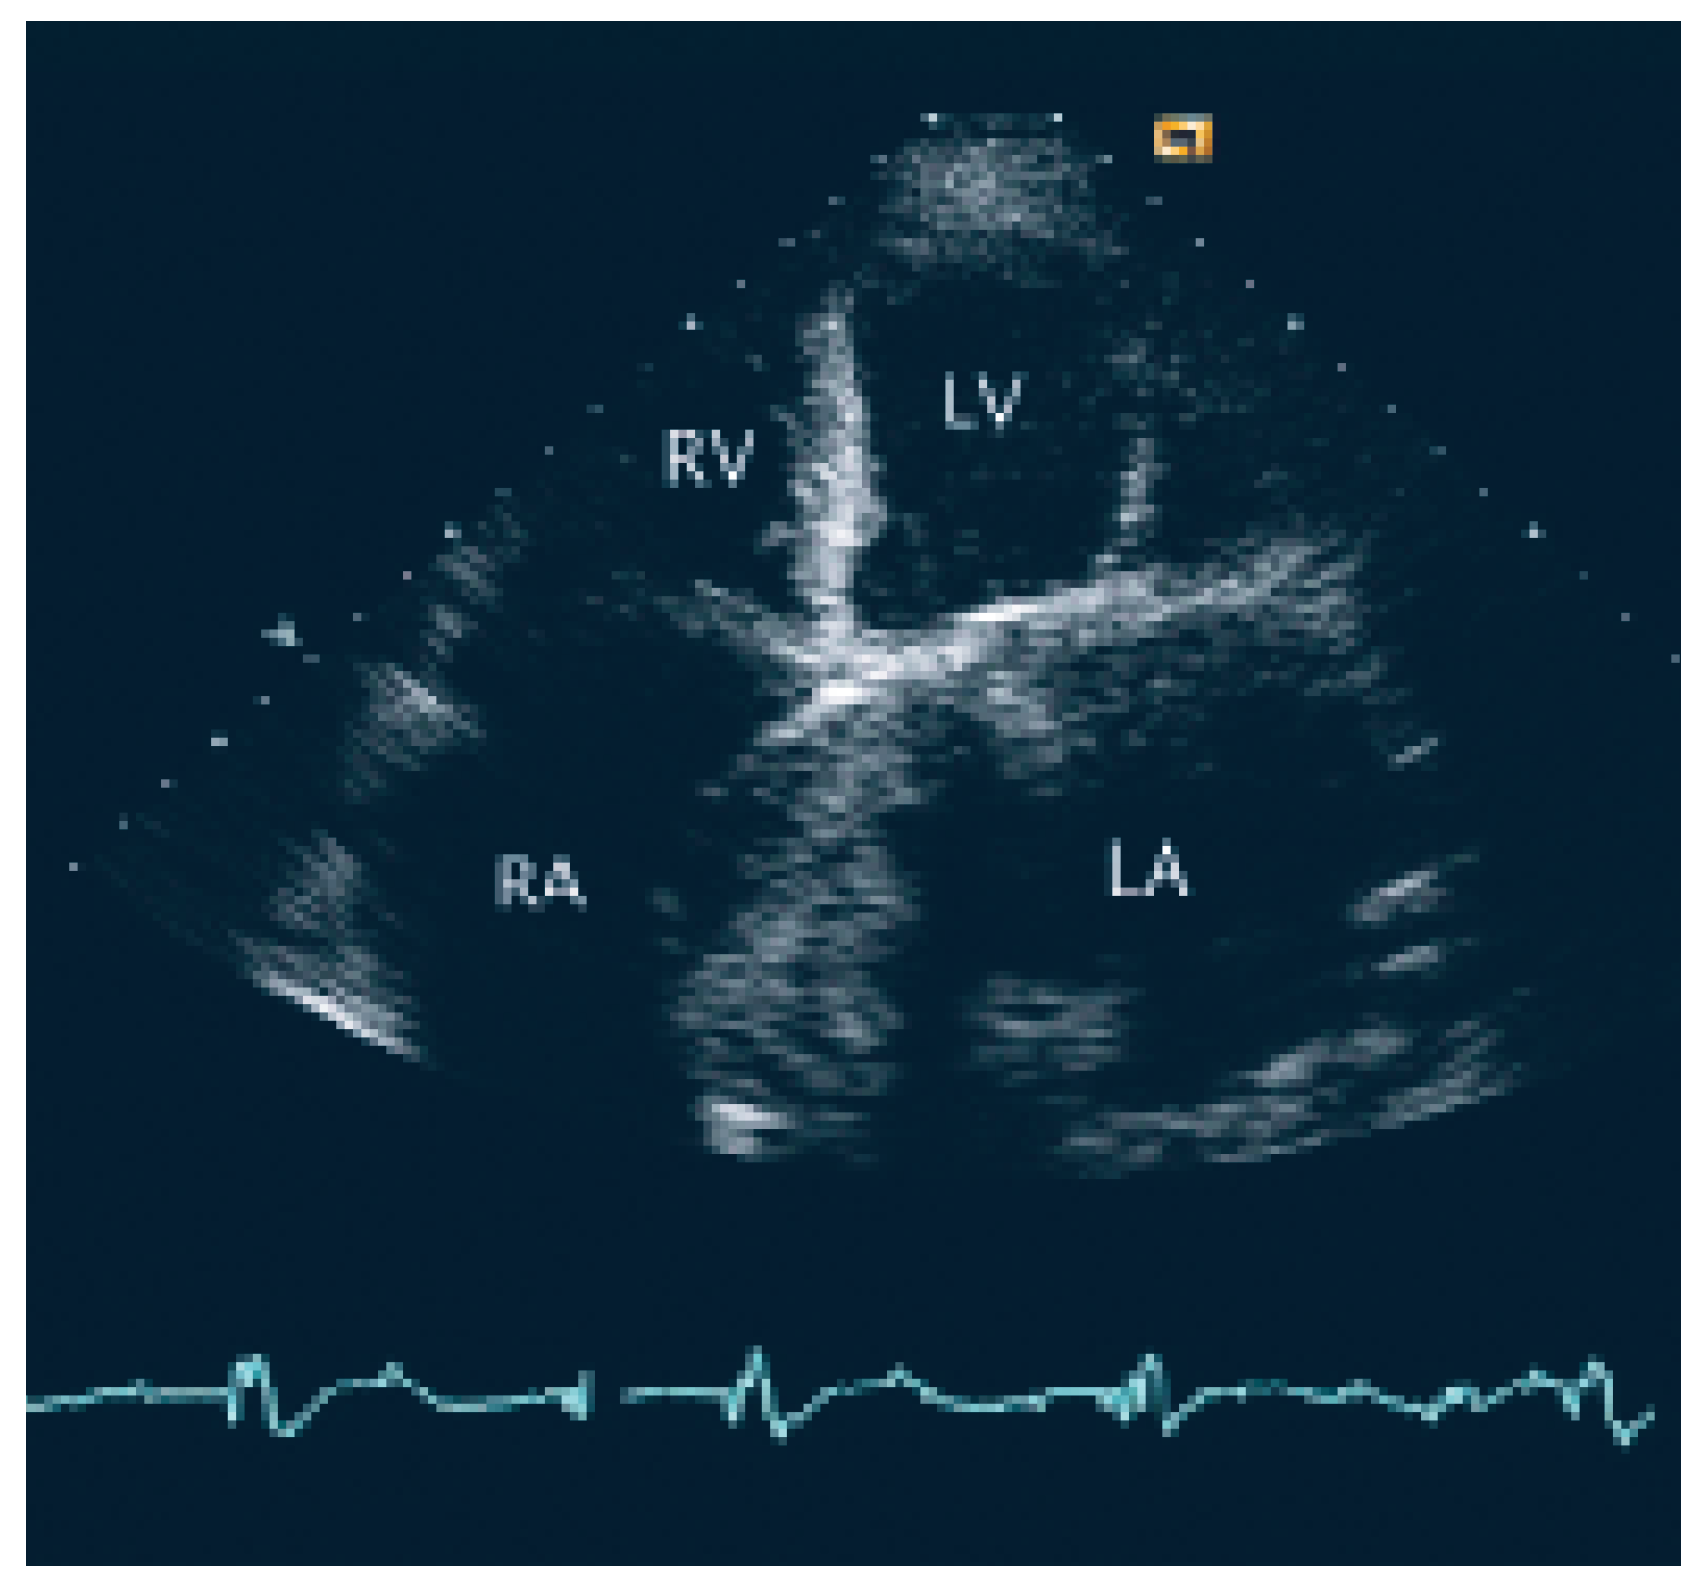

The patient was transferred to the intermediary care unit with the clinical diagnosis of subacute transmural anterior myocardial infarction. TTE showed a giant left atrium (9 cm × 12 cm × 9 cm; 509 cm3) and a large aneurysm of the atrial septum with compression of the right atrium (Figure 1) also as an apical scar, compatible with subacute myocardial infarction (Figure 1).

As cited in Hurst’s memories [1] “… giant left atrium is defined as one that touches the right lateral side of the chest wall. The condition is caused by rheumatic mitral valve disease and atrial fibrillation is always present …”. This case illustrates the pivotal role of echocardiography in defining and quantifying this pathology and the associated thromboembolic risk. TTE and particularly TEE allowed to assess the magnitude of the giant left atrium (Figure 1), the presence of spontaneous contrast and intracardiac thrombus (Figure 2 and 3), the presence of normal functioning of the mechanical valve prosthesis, and the occurrence of a new apical dyskinesia compatible with the diagnosis of acute myocardial infarction [2].

Figure 1. Transthoracic echocardiography shows a giant left atrium with a severe aneurysm of interatrial septum with displacement to the right. LA = left atrium; LV = left ventricle; RA = right atrium; RV = right ventricle.